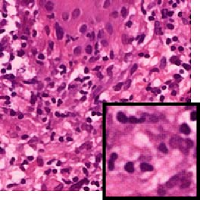

Leishmaniasis background and histology presentation. The World Health Organization (WHO) has selected cutaneous leishmaniasis as a neglected tropical disease (NTD) with growing, uncontrolled, and ignored infection affecting millions of people every year [14, 9]. It is unfortunately one of the world’s most neglected poverty-related diseases, affecting the poorest people in developing countries and it is associated with risk factors like malnutrition, immune system deficiency, migration, inadequate education, illiteracy, gender inequality, and a shortage of services [1]. Furthermore, only eight countries in the world contribute to 90% of leishmaniasis cases: Afghanistan, Algeria, Brazil, Iran, Pakistan, Peru, Saudi Arabia, and Syria [12]. It is a vector-borne infection caused by the protozoan parasite Leishmania. The vector is the female sand-fly. The lesions of cutaneous leishmaniasis vary in presentation ranging from a single self-limited skin lesion to multiple large destructive and ulcerated lesions on mostly the exposed parts of the body such as face, forearms, and lower legs [2]. Skin biopsy is considered the gold standard method for confirmation of diagnosis. The presence of large epitheloid granulomas and small hematoxylinophilic LD bodies (that are round, uniform in appearance, intracytoplasmic and sometimes distributed around the outer rim of the vacuoles) is critical for diagnosis and confirmation of leishmaniasis [4]. Large granulomas are visible at 10X but the smaller hematoxylinophilic bodies (around 3-4mm in size) are usually visible at 40X and can easily be missed if they are few in number, leading to misdiagnosis. Specialized dermatopathologists are the only ones who can diagnose these accurately based on patient history, clinical features, and laboratory diagnosis. It is thus critical to share the digitized slides of these cases from rural poor remote areas with dermatopathologists (mostly residing in urban centers) for quick diagnosis and accurate management of the patient.

We demonstrate our WSI creation workflow on Leishmaniasis cases, as shown in Figures 1 and 4. An expert pathologist reviewed the cases and annotated granulomas as well as LD bodies on the stitched images and our generated images in Figure 4. To show generalizability of our approach, we also show results on core biopsies of breast, duodenum, stomach, liver, and lymph nodes (Figure 5).